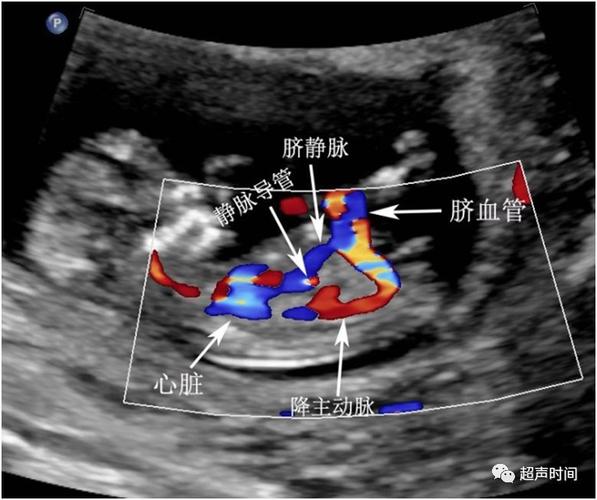

胎儿静脉导管血流

胎儿静脉导管血流,胎儿静脉导管血流频谱

胎儿静脉导管

胎儿静脉导管图

胎儿静脉导管解剖

胎儿静脉导管解剖图

胎儿静脉导管超声切面

胎儿静脉导管超声图片

静脉导管

静脉导管超声图

脐静脉导管